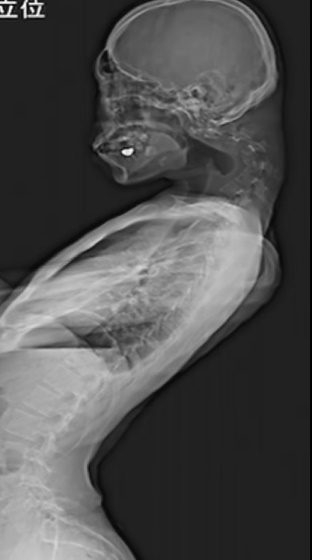

|

| 스마트폰으로 하루에 몇 시간씩 게임을 하던 20대 남성이 ‘머리떨굼 증후군’ 진단을 받았다. 목과 척추가 변형된 모습 [데일리 메일] |

하지만 이러한 생활 습관이 반복되면서 목과 척추뼈가 기이하게 꺾여 척추가 탈구되는 증상까지 나타났다. 탈구는 척추뼈 사이에 있는 인대나 추간판이 늘어나거나 찢어져 척추뼈가 열에서 벗어나는 것을 말한다. 또한 남성은 목뼈가 휘어지면서 목 뒤에도 혹이 생겼다.